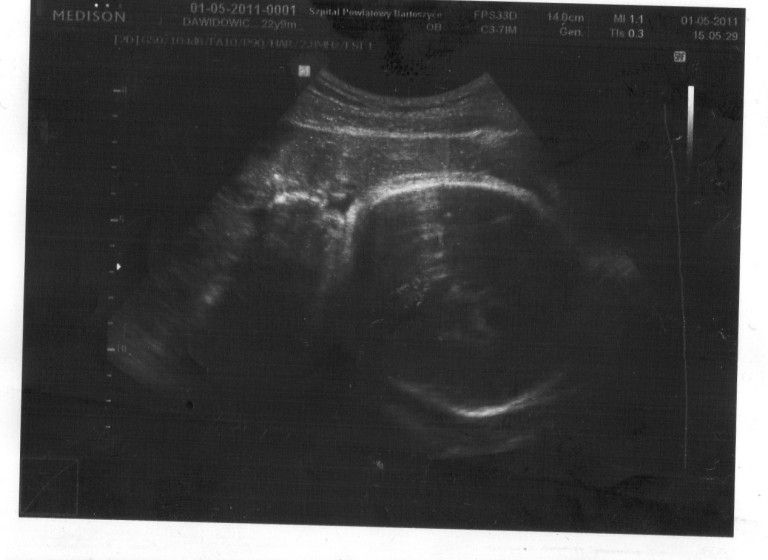

. Jak poszłam na wizytę do doktora cała się trzęsłam, powiedziałam mu o swoich obawach. Pan doktor na szczęście mnie uspokoił, zrobił usg i jak tylko zobaczyłam moją "fasolkę" na monitorze poczułam, że czeka mnie coś nowego, wspaniałego. Było to uczucie nie do opisania:-) Odetchnęłam, wróciłam do domku, zaczęłam rozmyślać o dziecku i w końcu się zarejestrowałam na familie

Na początku 8 miesiąca znów trafiłam do szpitala ze względu na bolący brzuszek, pan doktor stwierdził, że od tej pory mam "leżeć plackiem" i się nie przemęczać, wytrzymać do 37 tygodnia ciąży. Dziś jest 38 tydzień ciąży, "fasolka" okazała się być dziewczynką.